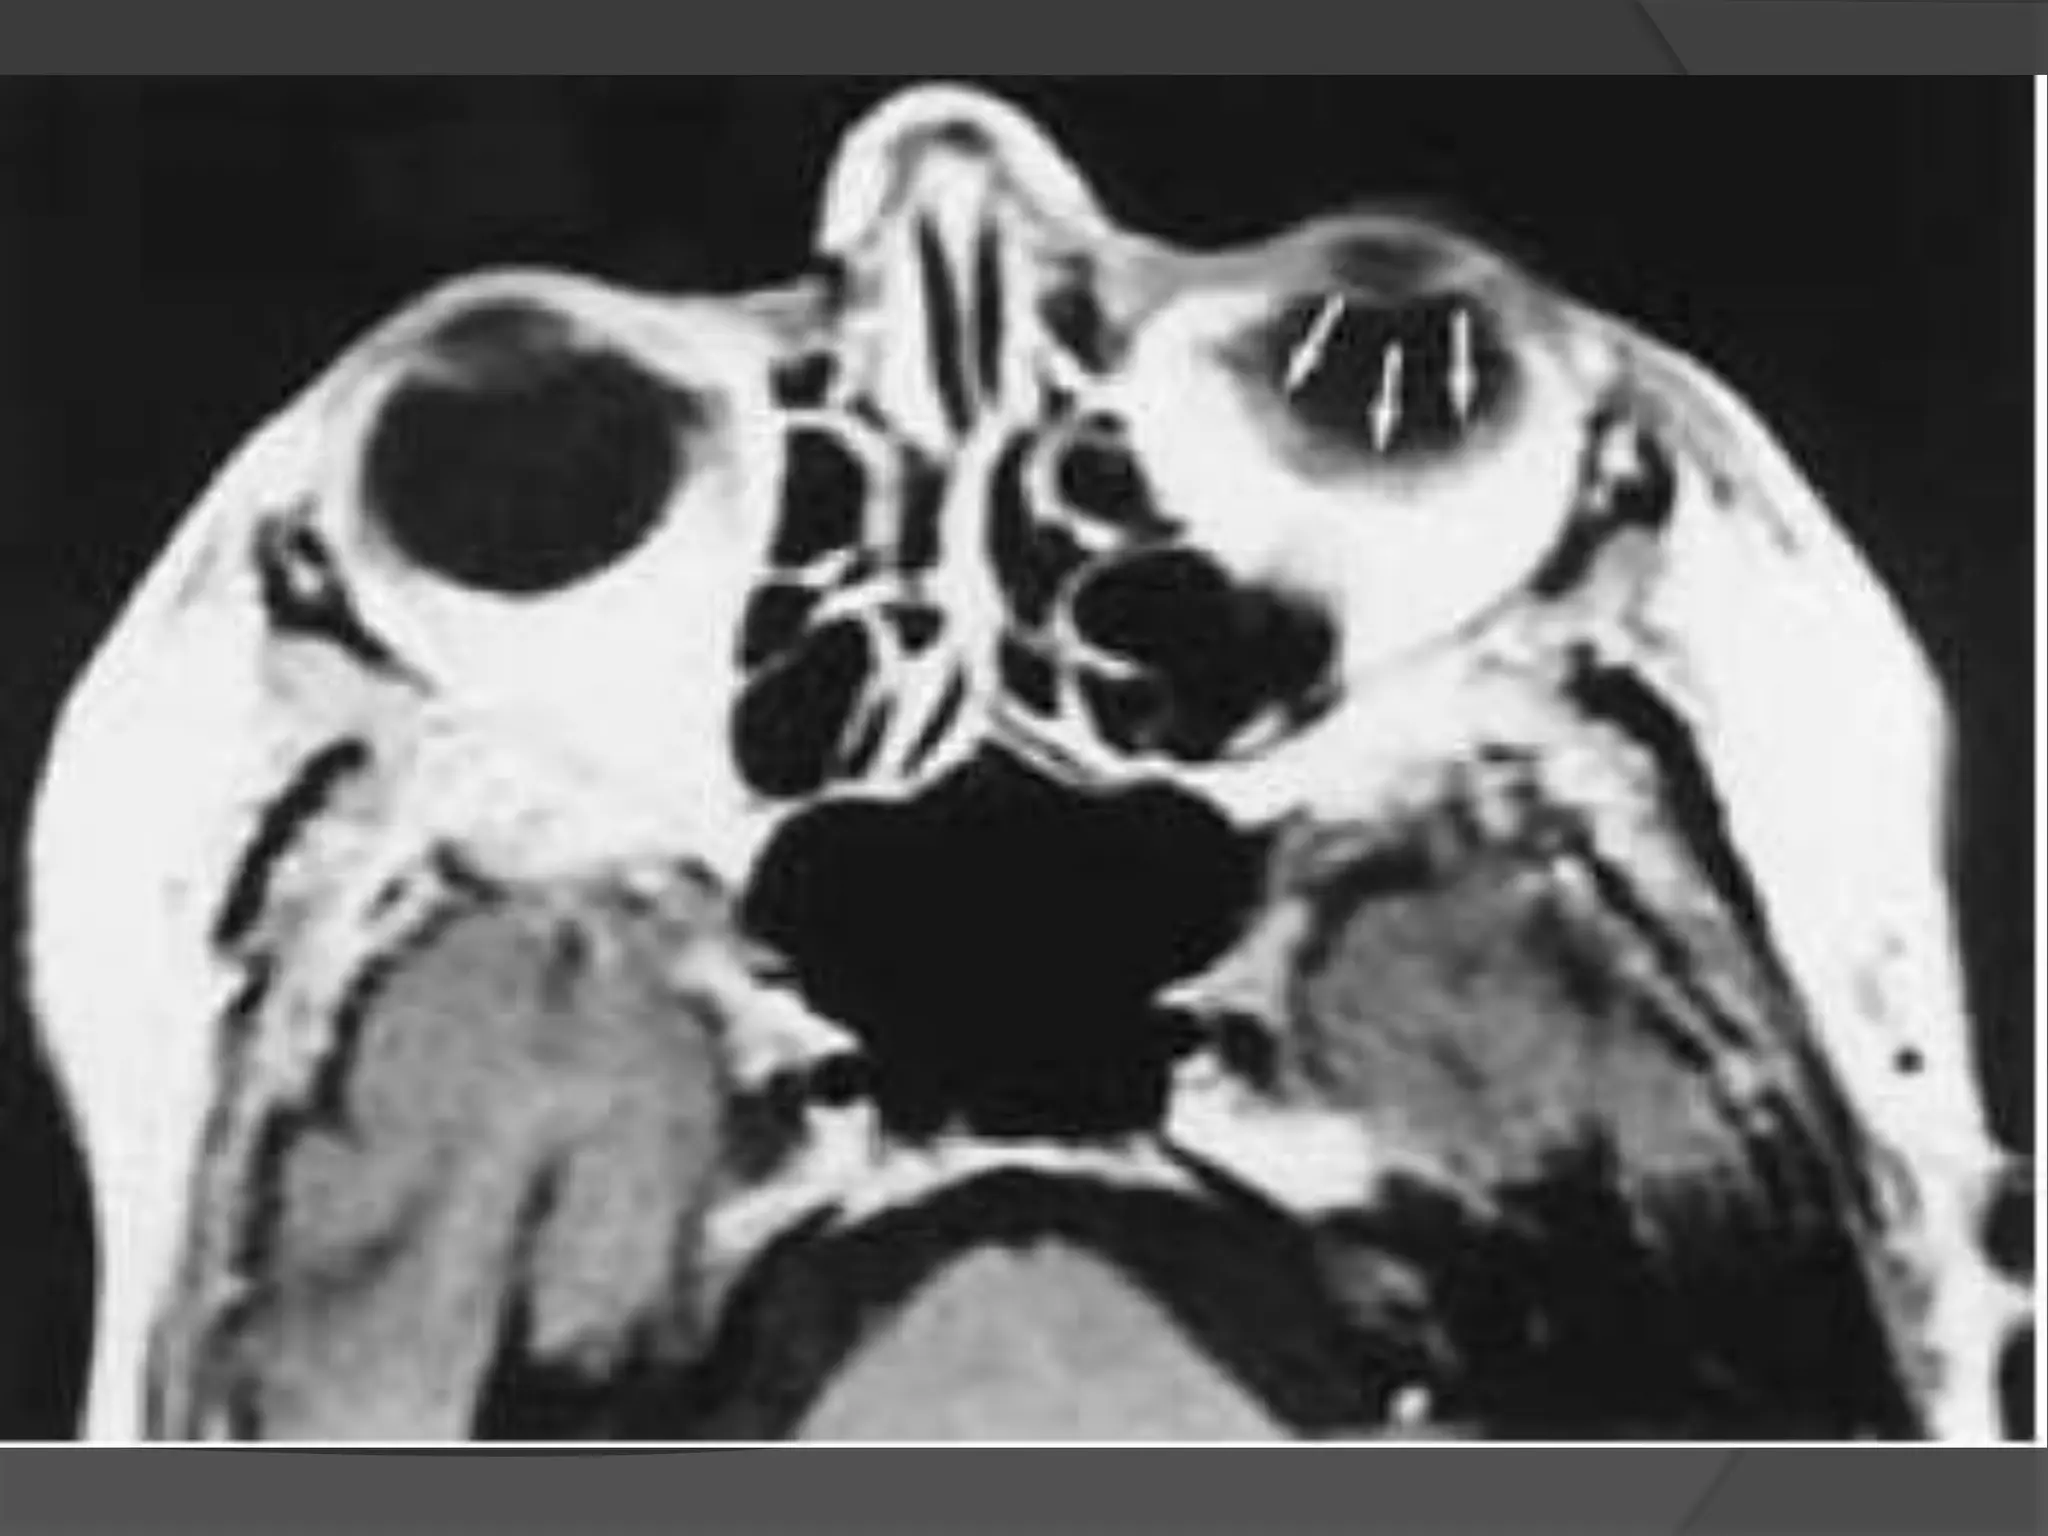

Rhabdomyosarcoma. CECT image

(A) Orbits demonstrates right proptosis due to large, lobular, intraorbital

mass.

(B) Image at lower level demonstrates invasion of right maxillary

sinus (asterisk) as well as extension through lateral orbital wall (arrow),

consistent with the aggressive nature of this tumor.

Rhabdomyosarcoma. CECT image (A)Orbits demonstrates right proptosis due to large, lobular, intraorbital mass. (B) Image at lower level demonstrates invasion of right maxillary sinus (asterisk) as well as extension through lateral orbital wall (arrow), consistent with the aggressive nature of this tumor.